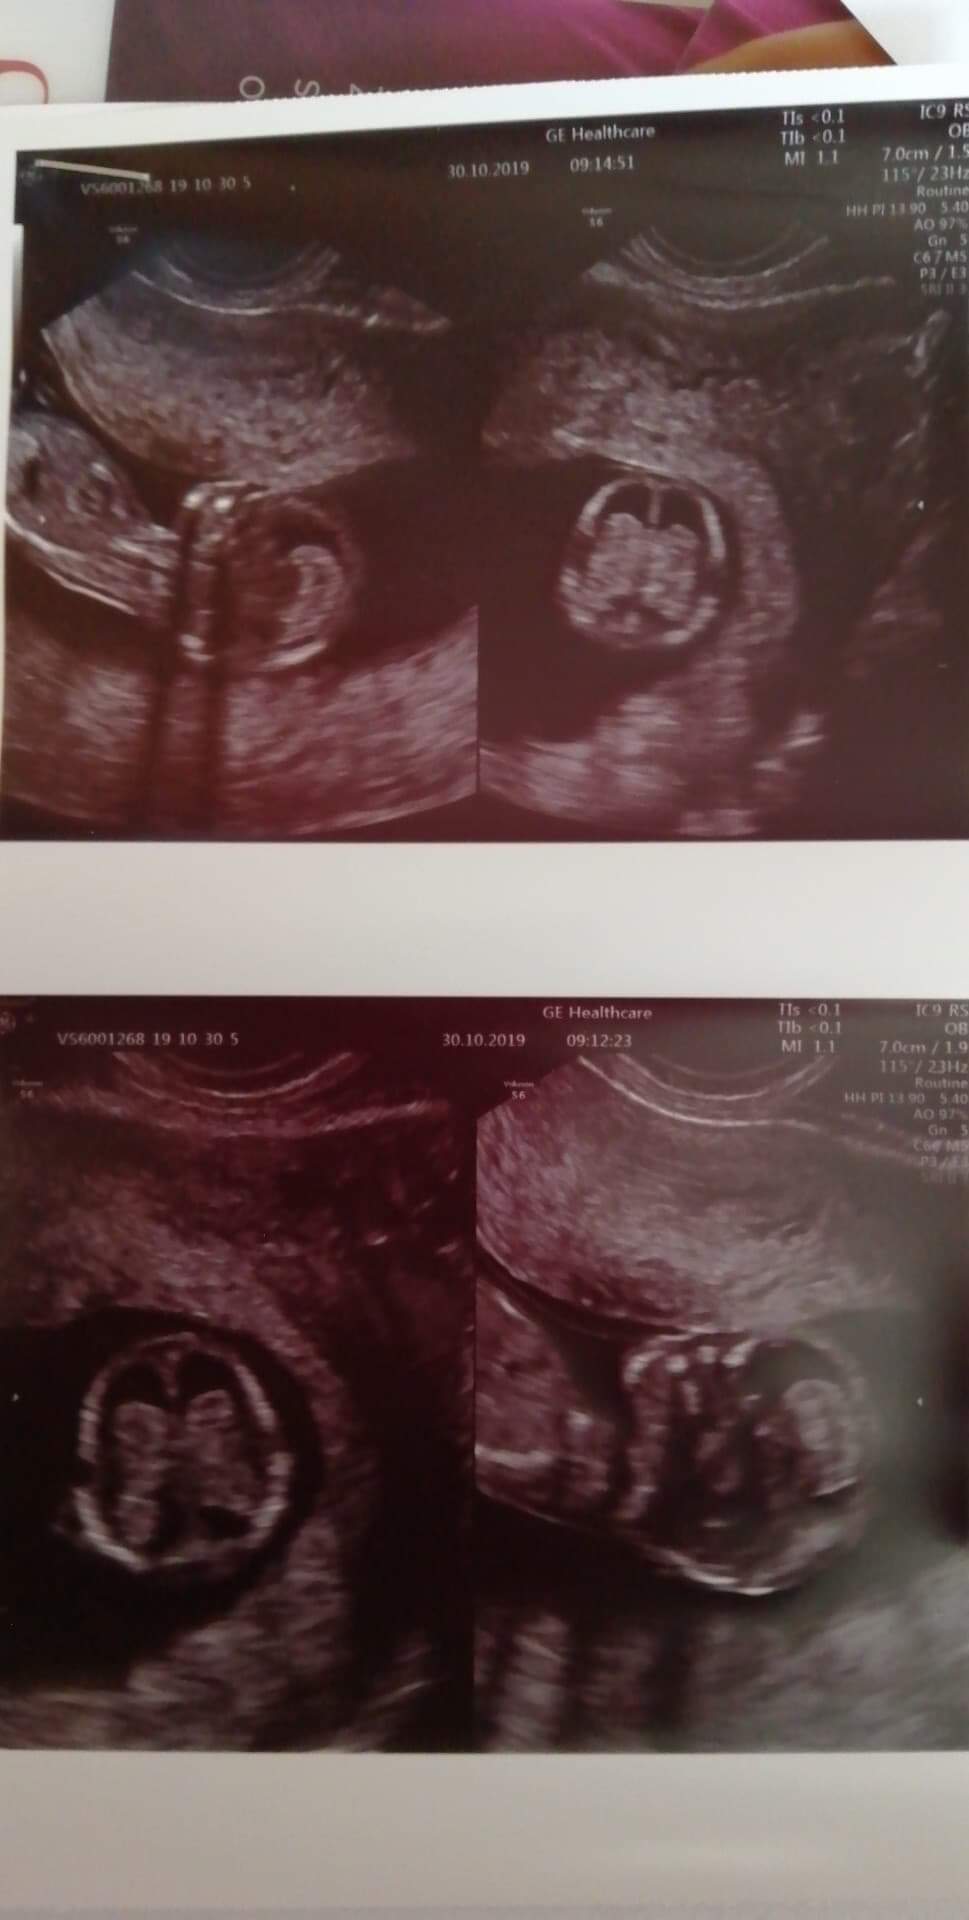

heh rączki nóżki A my spodziewaliśmy się małej fasolki ♡♡♡♡ tez sie uśmialiśmy